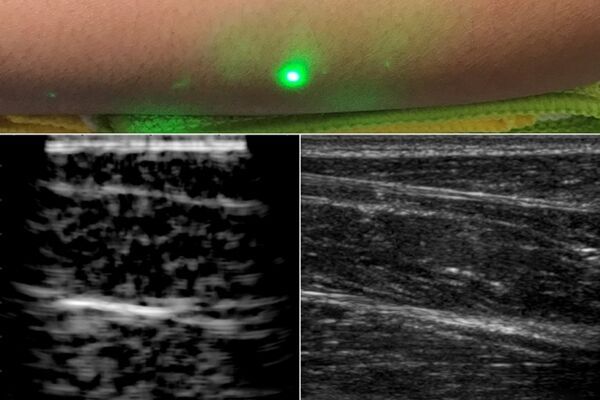

Researchers produce first laser ultrasound images of humans

"Technique may help remotely image and assess health of infants, burn victims, and accident survivors in hard-to-reach places. For most people, getting an ultrasound is a relatively easy procedure: As a technician gently presses a probe against a patient’s skin, sound waves generated by the probe travel through the skin, bouncing off muscle, fat, and other soft tissues before reflecting back to the probe, which detects and translates the waves into an image of what lies beneath. Conventional ultrasound doesn’t expose patients to harmful radiation as X-ray and CT scanners do, and it’s generally noninvasive. But it does require contact with a patient’s body, and as such, may be limiting in situations where clinicians might want to image patients who don’t tolerate the probe well, such as babies, burn victims, or other patients with sensitive skin. Furthermore, ultrasound probe contact induces significant image variability, which is a major challenge in modern ultrasound imaging. Now, MIT engineers have come up with an alternative to conventional ultrasound that doesn’t require contact with the body to see inside a patient." [...]